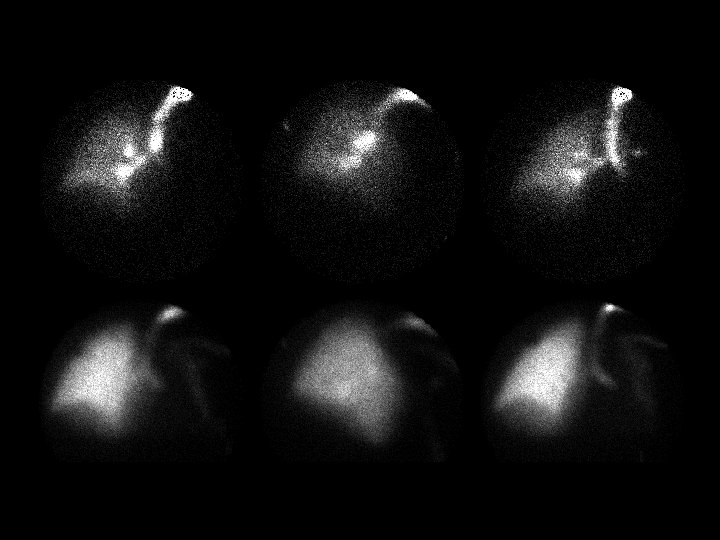

Bilateral pars fractures • Findings: – Planar images of the spine demonstrate subtle increased activity at L 5 – Coronal and axial SPECT images are diagnostic • ddx: – NONE! – This is an Aunt Minnie!